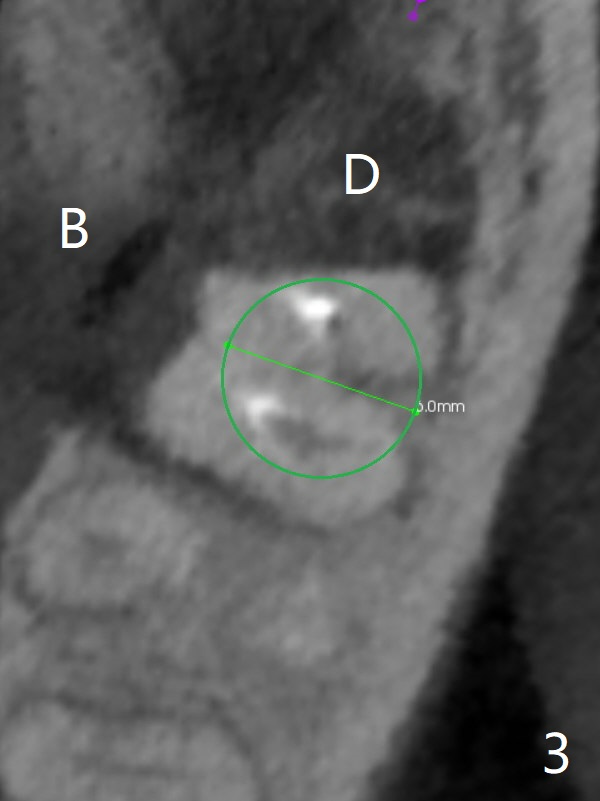

A 53-year-old man will return for #18 extraction and implant because of endo failure after the same treatment at #14 (Fig.1). It appears that the mesiolingual canal is missing for RCT (Fig.2 (coronal section at the mesial root)). Bony defect is buccodistal; try to place an implant as mesiolingual as possible (Fig.3 (axial section)). To reduce lingual (L) plate perforation and neuropathy (orange), the implant is expected to be 5-6x9 mm (Fig.4,5). Use 4 mm stopper from DIO Sinus Kit for osteotomy (Fig.1,4,5). If his vein is prominent, prepare PRF 1-2 tubes.